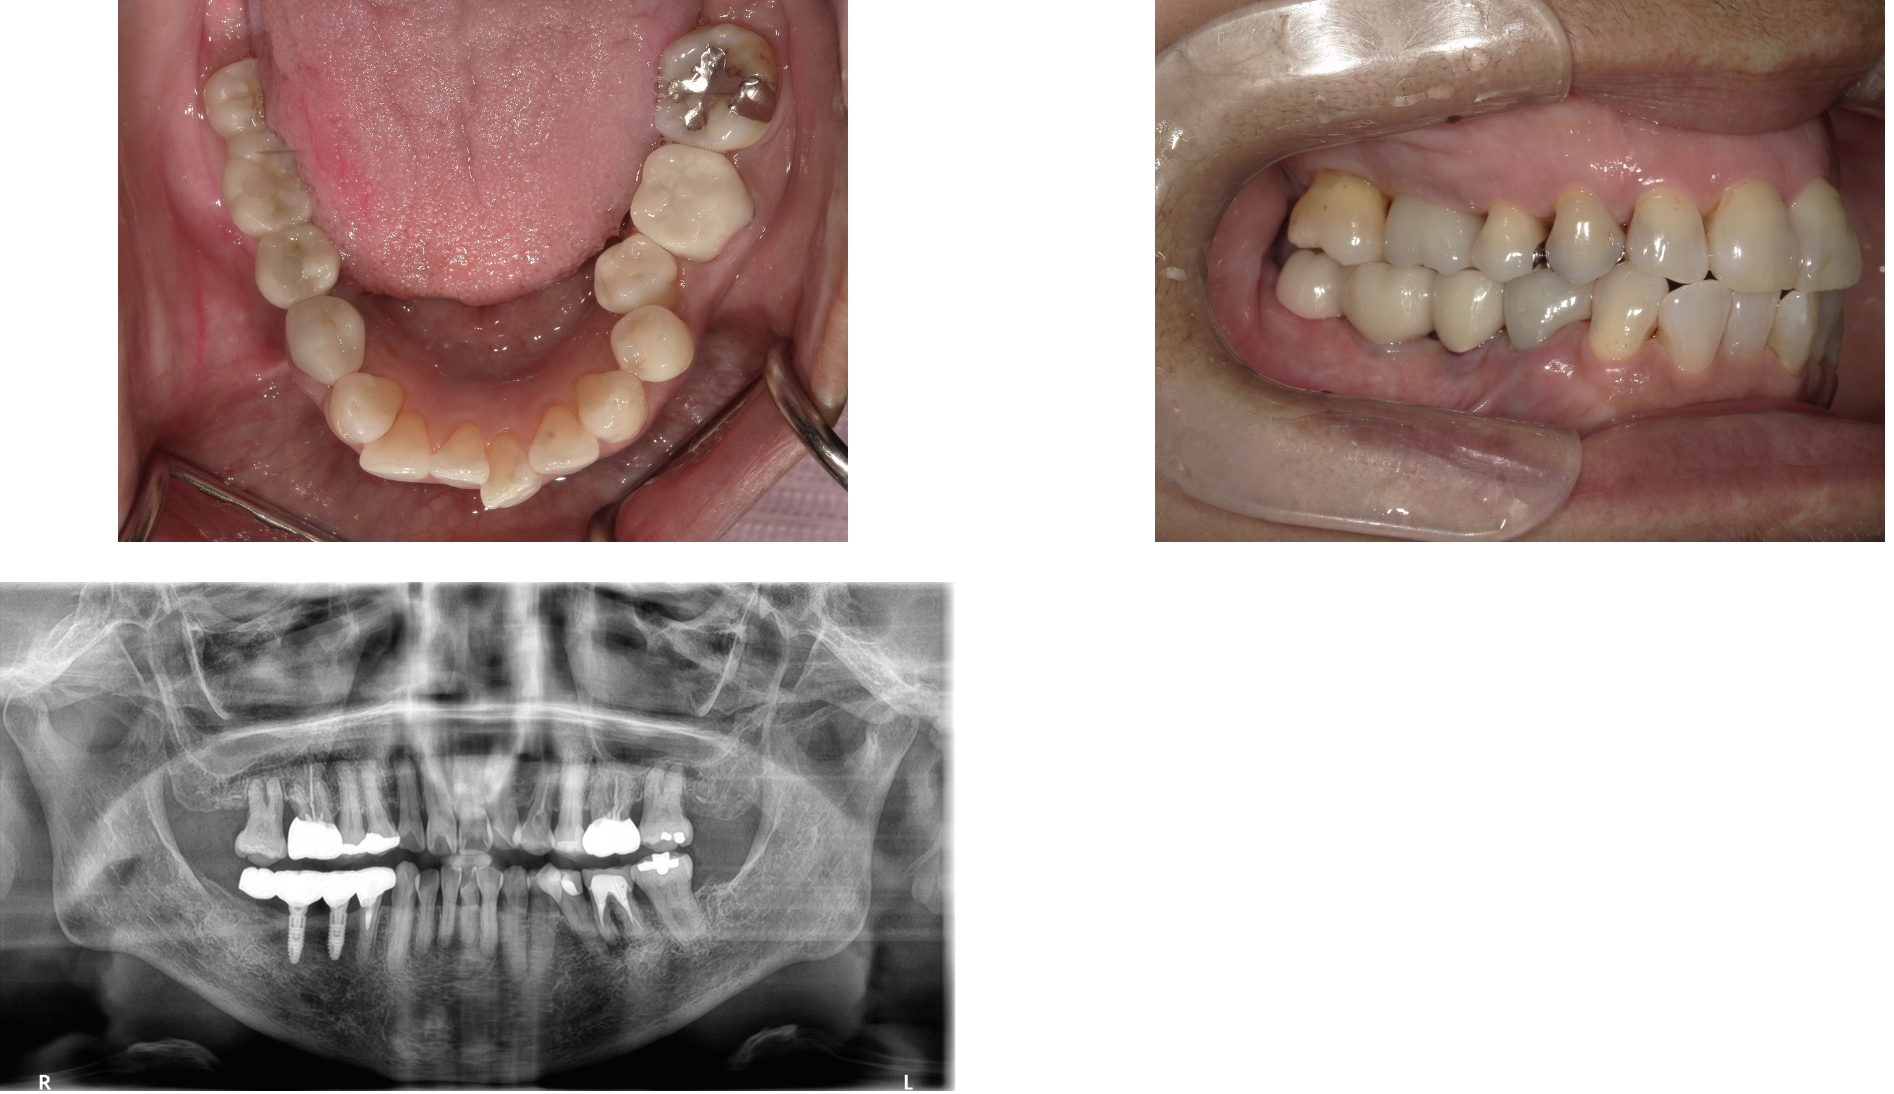

インプラント 症例4

右下56番にインプラントを行い、被せものはブリッジにした症例

虫歯で抜歯した歯にインプラントを行った